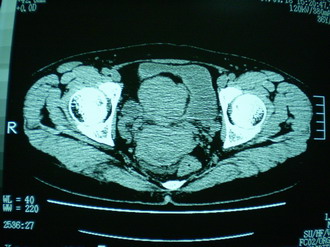

子宫增大,内可见类三角形低密度区,子宫后方可见类圆形团块状影,内部密度不均匀,可见靶样结构,结合病史考虑1子宫后方宫外孕(宫内假孕囊形成)2子宫肌瘤合并妊娠

子宫明显前倾,增大,宫颈增大呈分叶状。子宫直肠窝见不规则形水样低密度。(膀胱胀尿不理想)

考虑:1、宫颈部占位;

2、子宫直肠窝少量积液(盆腔炎所致)。

考虑肌瘤堵塞子宫颈管导致宫腔积液。

考虑:1、宫颈部占位(宫颈癌?);

2、子宫直肠窝少量积液。

1、前曲子宫,2、宫颈部占位?3、盆腔及右输卵管积液?宫内积血?4、左侧卵巢囊肿。